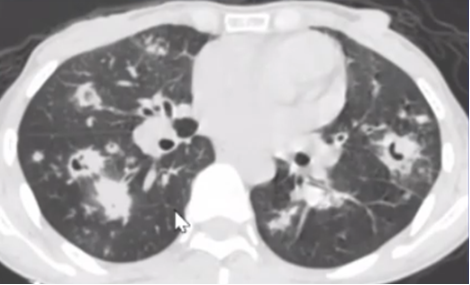

患者,男性,23岁。主诉:面色苍白5月余,乏力3月余,咳血丝痰2天,于2014年7月8日收住入院。患者于5月前无明显诱因出现面色苍白,无头晕、头痛、乏力、发热、咳嗽、咳痰等症状,无咽痛、腹痛、腹泻,面色苍白逐渐加重。查血常规示白细胞115.73×109/L,血红蛋白37 g/L,血小板59×109/L。腹部B超示肝脾大,骨髓穿刺结果示急性单核细胞白血病。患者于2天前无明显诱因出现发热,体温最高38.8℃,自行服退热药可降至正常。为求进一步诊治就诊于本院。确诊后予化疗,过程中出现咳嗽,发热。胸部X线片未见异常(图1)。患者入院第2天,胸部CT发现左上肺斑片状渗出性病变(图2)。提示感染性病变可能,临床采取抗感染治疗。

图片

图1  患者胸部X线片(2014-07-09)

图2  患者胸部CT(2014-07-10)